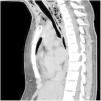

Paciente mujer de 17 años con antecedentes de meningoencefalitis en la infancia sin secuelas, que consultó por un cuadro clínico de una semana de evolución consistente en dolor cervical, odinofagia y fiebre de hasta 39°C. En la exploración física las constantes fueron estables, presentando dolor cervical a la movilización. En la analítica presentó elevación de reactantes de fase aguda. Se realizó una TAC cervical y torácica en la que se observó una gran colección cervical con abundantes burbujas de gas en su interior (figs. 1-3, asteriscos), con extensión hacia el mediastino posterior a través del espacio peligroso retrofaríngeo, hallazgos compatibles con fascitis necrosante y mediastinitis posterior. En las muestras quirúrgicas se cultivó Streptococcus dysgalactiae y S. intermedius. La paciente evolucionó favorablemente con tratamiento antibiótico y drenaje quirúrgico de la colección.